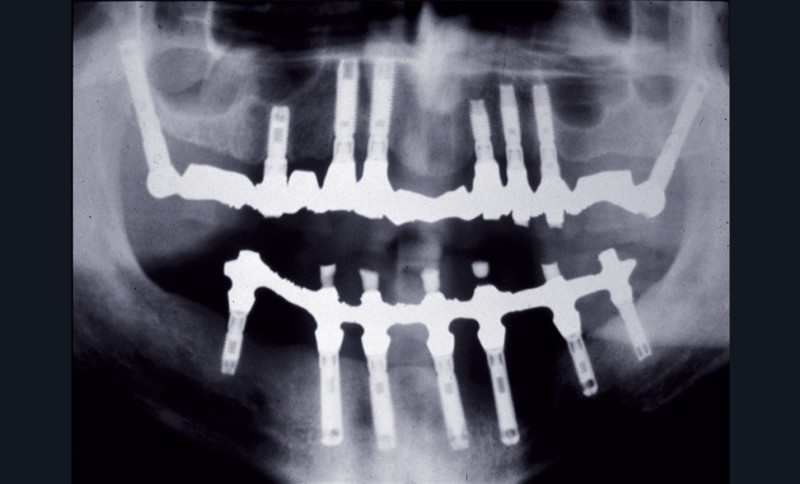

Trois mois plus tard, le patient s’inquiète de l’apparition d’une vaste masse tumorale dans la même zone (fig. 1).

Un cliché panoramique a été effectué (fig. 2). Il permettait de constater une vaste aire d’ostéolyse entourant l’implant et allant jusqu’à son apex. Ce patient était particulièrement ordonné : il avait conservé un cliché postopératoire révélant, autour du même implant, une structure osseuse absolument normale (fig. 3).